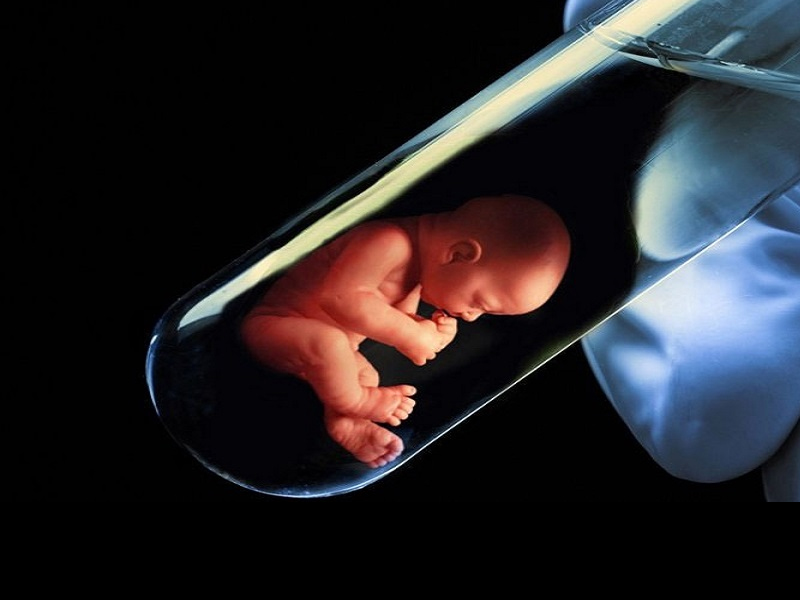

全球首批 用PS5手柄操控機器人 受精試管嬰兒出生